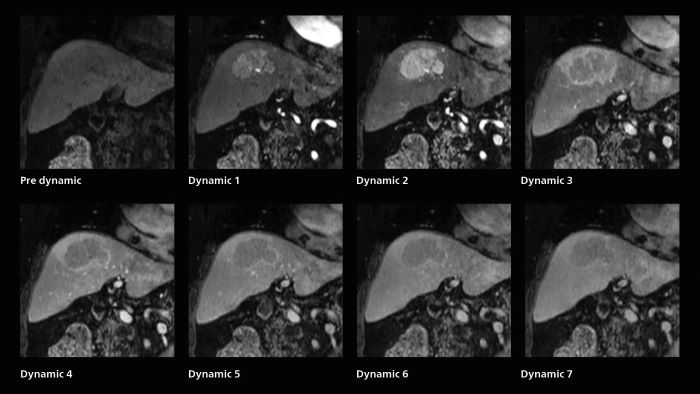

Rapid clarity for stroke and liver

Dynamic MRI of liver using SmartSpeed

A patient was referred for MR imaging of HCC. A double arterial volume dynamic study was performed. Since it is a volume dynamic study, it can also be evaluated using MPR images. Performed on Elition X.

The hospital’s routine ExamCard for dynamic MRI of the liver uses total scan duration 1:05 min, dynamic scan time 9.2 sec, 1.6 x 1.8 x 2.0 mm, 200 slices, acceleration factor 8.